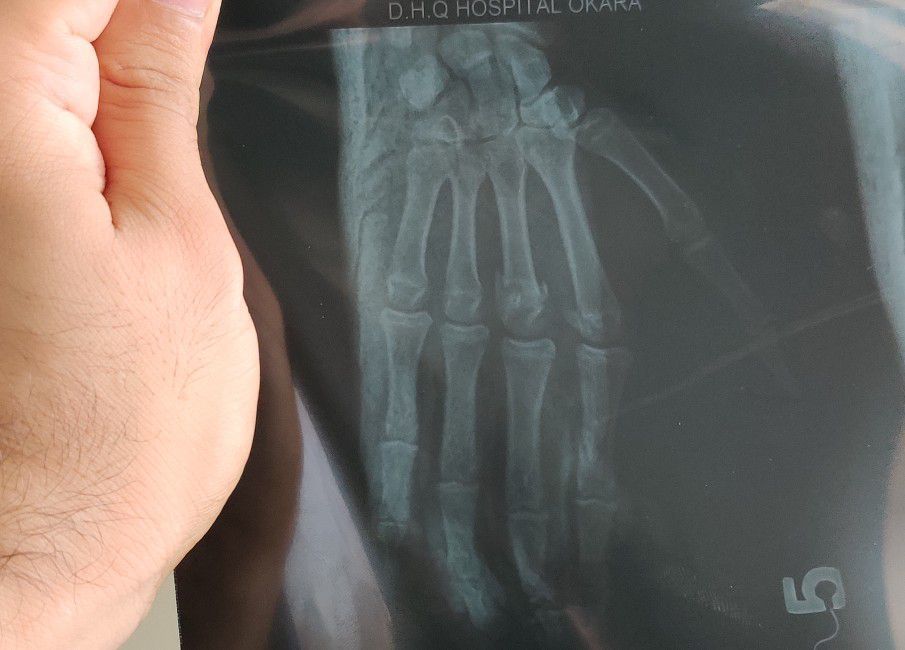

3rd Metacarpal Fracture

Hand

Ortho

Metacarpal